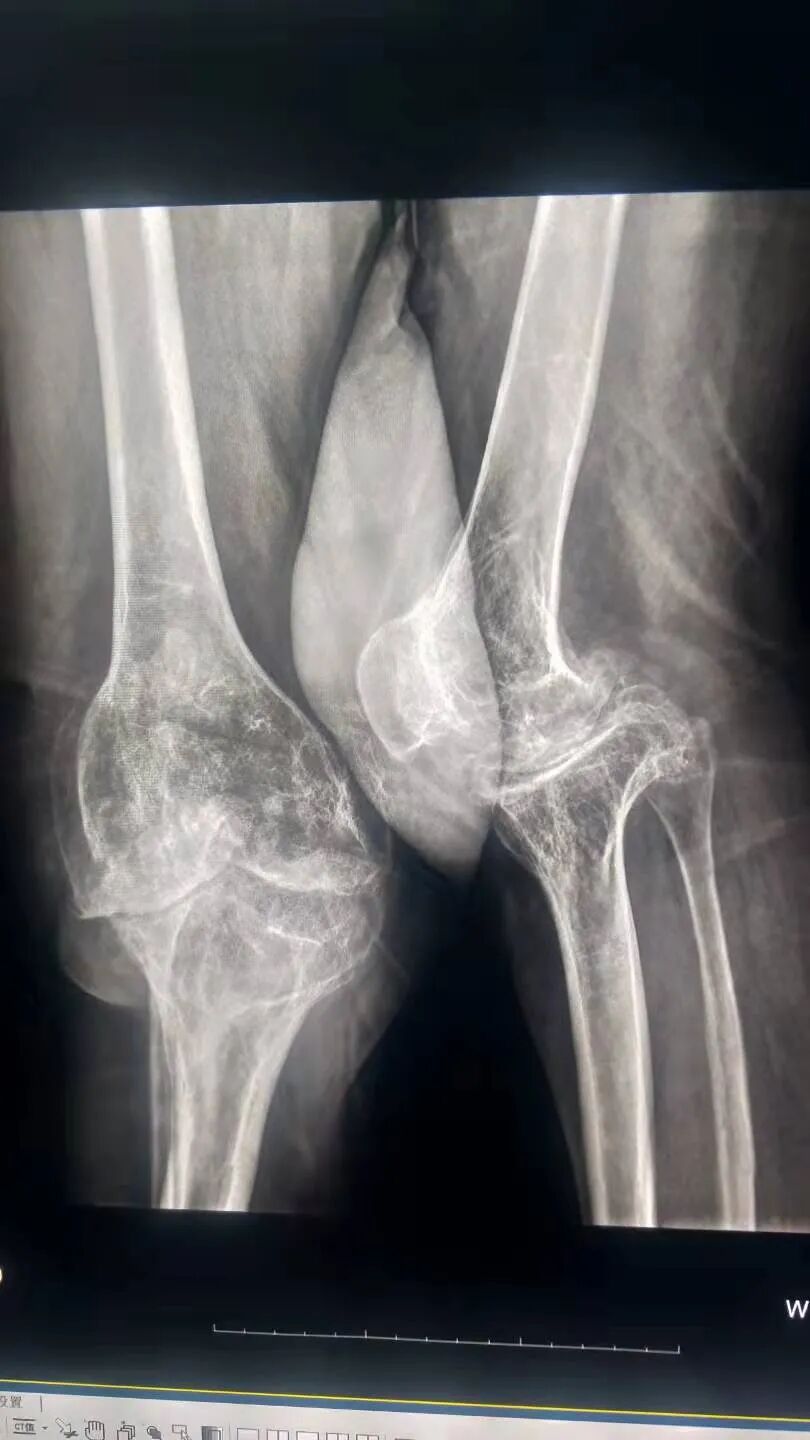

深入基层,助力大骨节病筛查工作

大骨节病是一种地方性、变形性疾病,在中国的青藏高原地区,大骨节病一度成为一种严重的地方病。大骨节病患者站不直、走不稳,严重者身材矮小、关节畸形粗大,甚至终身残疾,该病严重影响患者的生活质量和劳动能力。

图片图片

为贯彻党中央关于地方病防治工作的重要指示,9月6日至9月18日,林明医生作为柔性援藏医疗队的其中一员参与到西藏自治区大骨节病的救治救助行动中。历时13天,行走2500余公里,完成波密、察隅、墨脱3县5乡11个村的大骨节病筛查确诊工作,一共筛查大骨节病患者197例,为现存大骨节病患者下一阶段治疗工作的开展奠定坚实的基础。